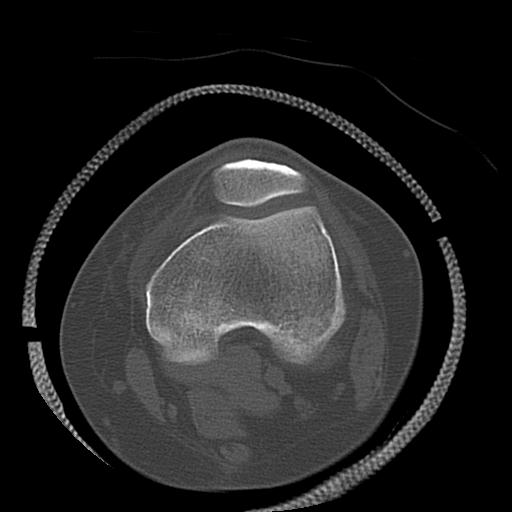

49554 3/13 膝 4R 3/16 4R 1/18 2R 78歳男性 膝蓋骨骨折